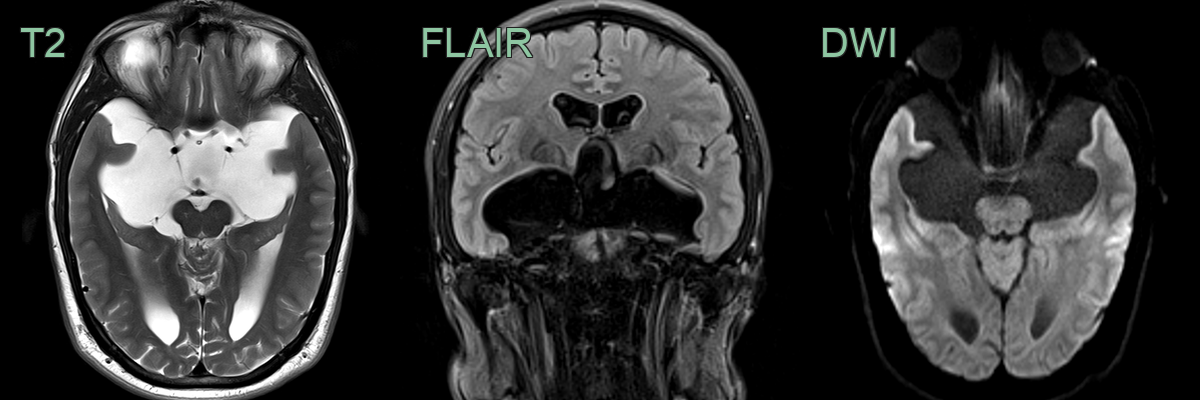

- MRI:

- CSF signal on all sequences (T2 hyperintensity with complete signal suppression on FLAIR)

- No soft tissue or post-gadolinium enhancement

- The wall is rarely seen although potentially visible on high resolution imaging (e.g., CISS)